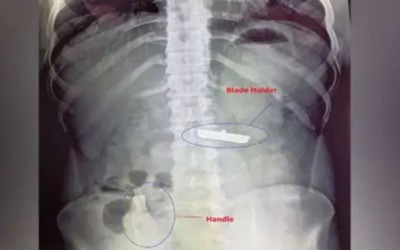

Chàng trai trẻ, mắc chứng trầm cảm và có ý định tự tử, đã nuốt vật nguy hiểm và phải nhập viện cấp cứu.